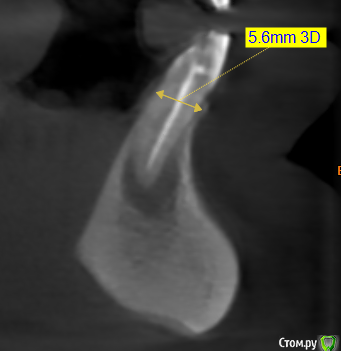

kramer Опубликовано 26 мая, 2020 Поделиться Опубликовано 26 мая, 2020 В общем, ситуация: 41, 42 бессимптомный периапикальный очаг, зуб 42 треснул. Биотип толстый. С точки зрения мезио-дистального расстояния влезает только 1 имплантат. Какой, на ваш взгляд, наиболее рациональный путь: а. Удаление обоих зубов, одномоментная имплантация 42, в последствии коронка с консолью б. Удаление обоих зубов, отсроченная имплантация в обл 42, в последствии коронка с консольюв. Удаление 41 с кюретажем, через пару месяцев удаление 42, одномоментная имплантация 42, в последствии коронка с консолью Ссылка на комментарий

red_butler Опубликовано 26 мая, 2020 Поделиться Опубликовано 26 мая, 2020 Я бы один поставил, одномоментно в позицию бокового резца 6 Ссылка на комментарий